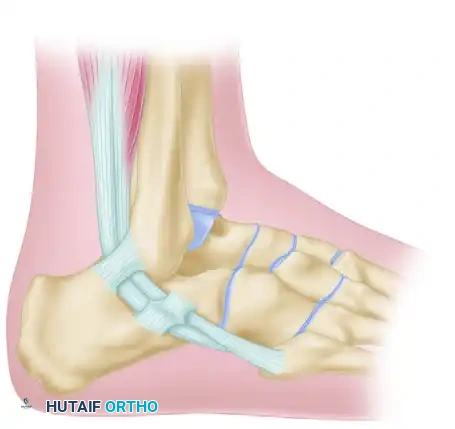

Step 6: Calcaneal Fixation

Pass the tendon deep to the peroneus longus tendon. The graft must now be secured to the lateral wall of the calcaneus to recreate the calcaneofibular ligament (CFL).

Drill a pilot hole into firm subchondral bone on the lateral aspect of the calcaneus. Select a 4-mm cancellous screw of appropriate length, paired with a spiked ligament washer.

Surgical Warning: Usually, a screw 30 mm long is sufficient. When measuring, add 3 to 4 mm to accommodate the thickness of the spiked washer. It is absolutely critical that the screw is not so long that it penetrates the medial calcaneal cortex, which could severely damage or tether the flexor hallucis longus (FHL) tendon or neurovascular bundle.

Pull the tendon inferior to the fibula to establish appropriate tension. Pass a No. 11 or No. 15 blade directly through the substance of the tendon to create a small slit. Insert the screw and washer through this slit. While maintaining strict traction on the tendon, advance the screw until the spiked washer gains firm, compressive purchase against the lateral calcaneal cortex. (If the lateral cortex is sclerotic, tapping may be required).

Step 7: Final Routing and Closure

Pass the remaining free end of the tendon (which is usually about 2 cm long) superficial to the peroneus longus tendon. Loop it back and attach it securely to itself at the tip of the fibula using multiple interrupted non-absorbable sutures.